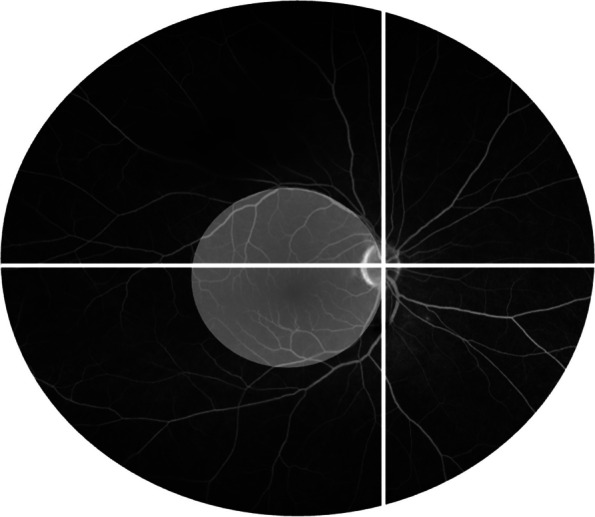

Methods: Eight patients (16 eyes) received TCZ and were included in the analysis. The primary outcomes measured were inflammatory activity in the retina and choroid, assessed by fluorescein angiography (FA) and indocyanine green angiography (ICGA) using the Angiography Scoring for Uveitis Working Group at baseline, 6, 12, 24, and 36 months.

Results: The mean follow-up time with TCZ treatment was 33 months. At baseline, the median FA score was 14 (quartiles: 10.25, 15.25), which significantly decreased over time (at 36 months: 8 (5.5, 11); p = 0.004). In contrast, the ICGA score significantly increased within the first year (median at baseline: 5 (4.75, 7.25); at 6 months: 7 (6, 9.25); at 12 months: 7 (6.5, 9.25); p = 0.002), but returned to baseline levels after two years (at 24 months: 5 (5, 6.5); at 36 months: 5.5 (4, 7.5)). Central retinal thickness (CRT) improved significantly after 6 months (median at baseline: 295 µm (275, 322); at 6 months: 275 µm (251, 308); p = 0.01).